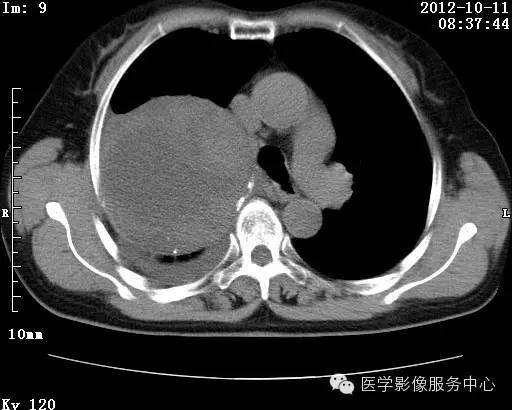

【病例】右肺巨大错构瘤1例CT影像表现

病史:女 65岁咳嗽咳痰 右肺巨大肿块就诊。

错构瘤的主要组织成分包括软骨、脂肪、平滑肌、腺体、上皮细胞,有时还有骨组织或钙化。错构瘤一般为实质致密的球形、卵圆形,也可以是分叶状或结节状,大多数直径在3cm以下。

错构瘤的发病年龄多数在40岁以上,男性多于女性。 绝大多数错构瘤(约80%以上)生长在肺的周边部,紧贴于肺的脏层胸膜之下,有时突出于肺表面。其特征钙化为爆米花样钙化,内有脂肪软骨成分等等。最常见的部位是胸膜下肺实质内,其次为主支气管或肺叶、肺段支气管内。

瘤内出现“爆米花样钙化”是诊断的主要指标之一。早期的点状、斑片状及结节状钙化 随时间增加钙化数量及范围会增加,最终可能演变 为爆米花样钙化;

另一项主要指标是瘤测得脂肪成分是诊断错构瘤。